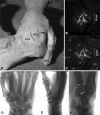

Methods: We addressed the morphology, load, and movement of the human thumb, emphasizing the CMC joint in normal and arthritic states. We present comparative anatomy, gross dissections, microscopic analysis, multimodal imaging, and live-subject kinematic studies to support or challenge the current understanding of the thumb CMC joint and its predisposition to disease.